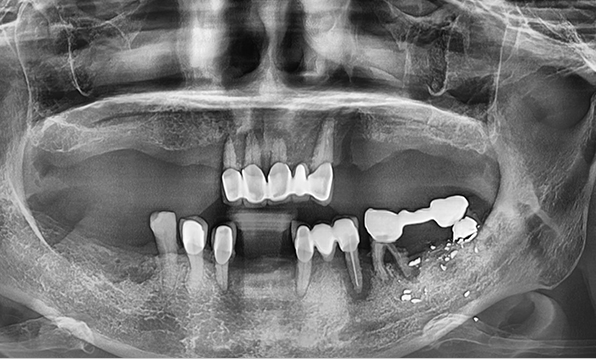

Before & After

Case 01

Before After